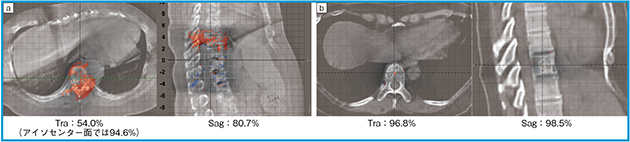

図3に,下部胸椎に対する自由呼吸下と固定シェルを用いた腹部圧迫による呼吸抑制下におけるガンマ解析(1%/1mm, threshold 80%)の画像,およびガンマパス率の結果を示す。横隔膜レベルにおいて,モーションアーチファクトによる線量計算誤差が呼吸抑制によって改善していることが確認できる。呼吸性移動の大きい部位において,その影響に対する対策について検討する必要がある。

図3 HS-CBCT画像とガンマ解析(1%/1mm, threshold 80%)のマージ画像(Traは横隔膜レベル)およびガンマパス率

a:自然呼吸下 b:固定シェルを用いた腹部圧迫による呼吸抑制下